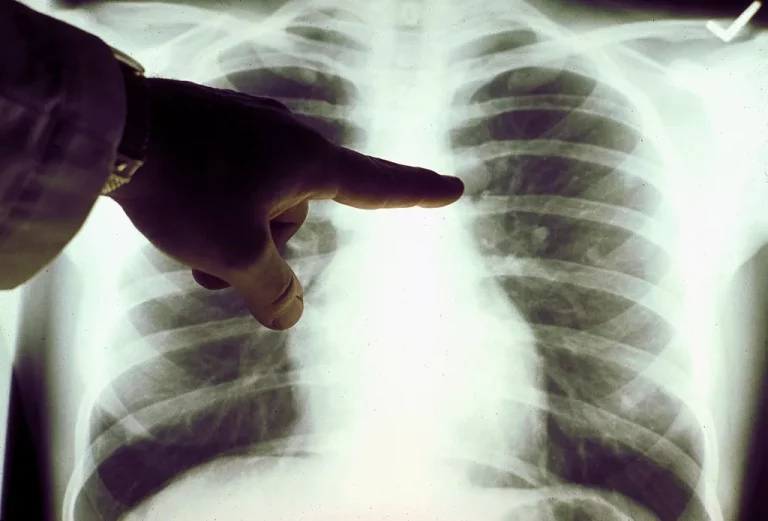

Exame referência mundial e recomendado pela OMS para identificar a doença em sua fase sem sintomas, já...